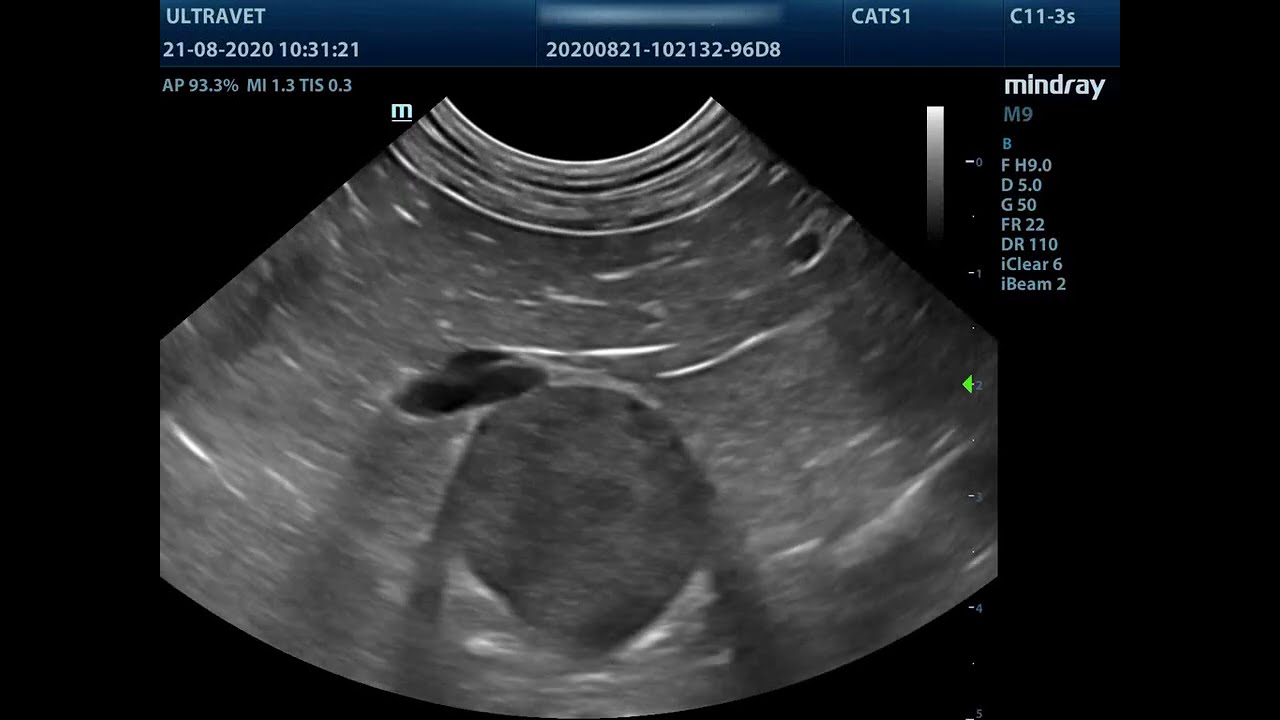

Enlarged Adrenals In Dogs . Bilateral adrenomegaly (>0.8 cm caudal pole widths) has been. Also known as cushing’s disease or. The most common cause (85% to 90% of cases) is a tumor in the. An abdominal ultrasound examination lets your veterinarian see the adrenal glands and determine. Fortunately, with proper treatment, dogs diagnosed with addison’s. Hypoadrenocorticism, more commonly known as addison’s disease, is a disease has serious consequences for dogs. Longitudinal axis view of the left adrenal gland of a dog with a mildly enlarged caudal pole (calipers), measuring 0.84 cm in height. Increased cortisol levels in dogs may result from one of several mechanisms. Named after a neurosurgeon who first described the syndrome in people in 1912. As patients in addisonian crisis are collapsed and hypovolaemic, they require rapid volume expansion, so a fluid bolus is likely to be.

Adrenals in Dogs Ultrasound approach and anatomy with 3D animations Enlarged Adrenals In Dogs Longitudinal axis view of the left adrenal gland of a dog with a mildly enlarged caudal pole (calipers), measuring 0.84 cm in height. The most common cause (85% to 90% of cases) is a tumor in the. Named after a neurosurgeon who first described the syndrome in people in 1912. As patients in addisonian crisis are collapsed and hypovolaemic, they. Enlarged Adrenals In Dogs.

Ultrasounding the Adrenals in Dogs YouTube Enlarged Adrenals In Dogs Longitudinal axis view of the left adrenal gland of a dog with a mildly enlarged caudal pole (calipers), measuring 0.84 cm in height. Also known as cushing’s disease or. An abdominal ultrasound examination lets your veterinarian see the adrenal glands and determine. Fortunately, with proper treatment, dogs diagnosed with addison’s. The most common cause (85% to 90% of cases) is. Enlarged Adrenals In Dogs.

Westbridge canine cushing disease adrenal gland ultrasound Enlarged Adrenals In Dogs Also known as cushing’s disease or. Named after a neurosurgeon who first described the syndrome in people in 1912. An abdominal ultrasound examination lets your veterinarian see the adrenal glands and determine. As patients in addisonian crisis are collapsed and hypovolaemic, they require rapid volume expansion, so a fluid bolus is likely to be. Longitudinal axis view of the left. Enlarged Adrenals In Dogs.